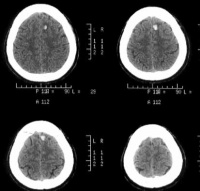

右侧颞叶脑挫裂伤

CT扫描[编辑 | 编辑源代码]

对脑挫裂伤与脑震荡可以作出明确的鉴别诊断,并能清楚地显示脑挫裂伤的部位、程度和有无继发损害,如出血和水肿情况。同时,可根据脑室和脑池的大小、形态和移位的情况间接估计颅内压的高低。尤为重要的是,对一些不典型的病例,可以通过定期CT扫描,动态地观察脑水肿的演变或迟发性血肿的发生。近年来,在有此设备的医院CT已作为急性头伤的常规检查,因为单靠伤史和查体难以作出超早期诊断。Stein等(1990)指出在GCS13~15危害较小的轻型头

右额颞叶脑挫裂伤合并蛛网膜出血

伤中,首次CT的阳性发现率竟占18%,并有5%需行手术治疗,强调早期CT检查的必要性。